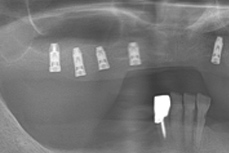

• インプラント

当院の医師は公益社団法人日本口腔インプラント学会・公益社団法人日本歯科先端技術研究所の会員です